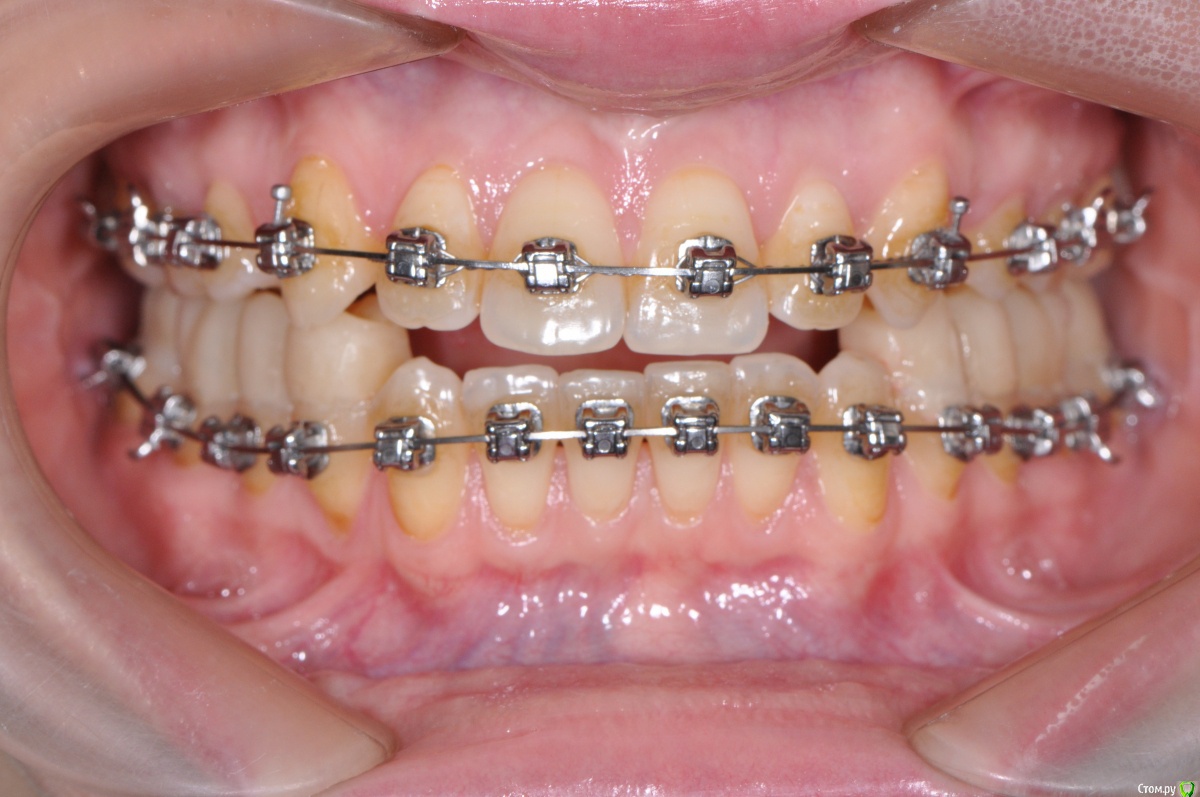

losenok83 Опубликовано 4 сентября, 2016 Автор Поделиться Опубликовано 4 сентября, 2016 Здравствуйте, очень нужна ваша помощь снова! Я обошла много ортодонтов в своем городе на предмет дальнейшего лечения. В конце концов мое самочувствие более менее менее улучшилось только после ортотика. В дальнейшем мне сказали ортодонт поставит мои зубы на такую высоту. Скажите пожалуйста это правда возможно, на такую высоту вытянуть свои верхние и нижние зубы? И еще изначально этот ортодонт планировала что в этом ортотике Н,Ч, выйдет вперед , а потом ее расширят. Поскольку этого не произошло, сказала что просто раздвинут место для раннее удаленных 4-рок на В,Ч. пружинами. А я очень боюсь, что в результате зубы будут торчать вперед как раньше.Разве нет? Расчет ТРГ на данный момент лечения. И вид челюстей в ортотике. Ссылка на комментарий

Skip Опубликовано 7 сентября, 2016 Поделиться Опубликовано 7 сентября, 2016 Алексей Олегович, а что вы могли бы сказать по моему случаю? И может вы знаете хорошего ортодонта в Ростове или области? И я уже наверное даже согласна на Краснодар! Если я правильно понял, то доктору удалось добиться положительной динамики со стороны ВНЧС? Если да, то это здорово. И необходимо удерживать это состояние бессимптомности с ортотиком минимум 12 мес. Завершающим этапом, как Вам и предлагали доктора, зубоальвеолярная экструзия нижних зубов или постоянный ортотик, включая покрытие им резцов и клыков. Ссылка на комментарий

losenok83 Опубликовано 8 сентября, 2016 Автор Поделиться Опубликовано 8 сентября, 2016 Yana guapa, Skip. С ортотиком, перестал хрустеть, щелкать сустав. И болит гораздо реже. Голова с шеей тоже чувствуют себя лучше, но может тут остеопат больше даже помог. Я надеялась, что и ушам полегчает, но пока шум, заложенность и звон все так же присутствуют. И ортотик мне уже постепенно убирать собираются через пару месяцев. Ссылка на комментарий